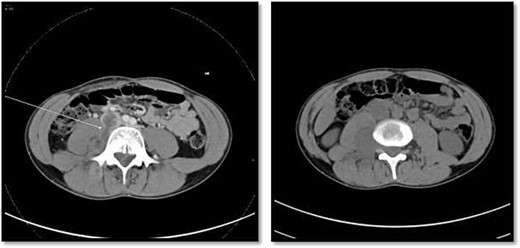

CT scan showed there is 4 × 3 cm lobulated mass noted at the right paravertebral space invading the right psoas muscle at the level of L3 and L4 and extending through the neural foramina, the associated with epidural component compressing the spinal cord from the level of the L2–L4.

An 18-year-old healthy man presented to the emergency department (ED) with 1-day history of right testicular pain and vomiting with no fever nor abdominal pain. Physical examination showed mild tenderness in the right testis, no swelling, normal longitudinal position and cremasteric reflex. Scrotal Doppler ultrasound was performed and showed reduced vascularity in the right testis and the left testis was normal. Moreover, the size and echogenicity were maintained for both testes (Fig. 1). Two months prior to this presentation, the patient presented with the same attack with only mild tenderness in the right testis, and all investigations were within normal limits and he was discharged with oral analgesic drugs. The decision was made to undergo surgical exploration for possible torsion/detorsion of the right testis. The patient was transferred immediately to the operating room for bilateral orchiopexy. The right spermatic cord was engorged with no evidence of ischemia identified and bilateral orchiopexy was done successfully. After the surgery, the patient was kept for observation for 24 h and then discharged. After 2 days from the surgery, the patient came back to ED with testicular pain and post-surgical swelling. We decided to do computerized tomography (CT) scan of the abdominal and pelvis to rule out retroperitoneal pathologies or referred pain. The CT showed 4 × 3 cm lobulated mass noted at right paravertebral space invading the right psoas muscle at the level of L3 and L4 (Fig. 2). The CT scan also showed there is an associated fistula tract between the mass and infrarenal inferior vena cava with thrombosis associated with epidural component extending through the neural foramina compressing the spinal cord from the level of the L2–L4 (Fig. 3). The patient was referred to spinal surgery and CT-guided paraspinal lumbar biopsy was taken. The histopathology came with the diagnosis of Ewing sarcoma. The decision was made by the medical oncology to start on a systemic chemotherapy (vincristine + Adriamycin + cyclophosphamide alternating with ifosfamide + etoposide (VAC/IE)) regimen. After six cycles, the follow-up magnetic resonance imaging demonstrated significant resolution of the right psoas and posterior paraspinal metastatic disease. In addition, further resolution with residual intraspinal extradural metastatic disease noted at right L2–3 and L3–4 levels. The patient is still followed up as an outpatient clinic with medical oncology.